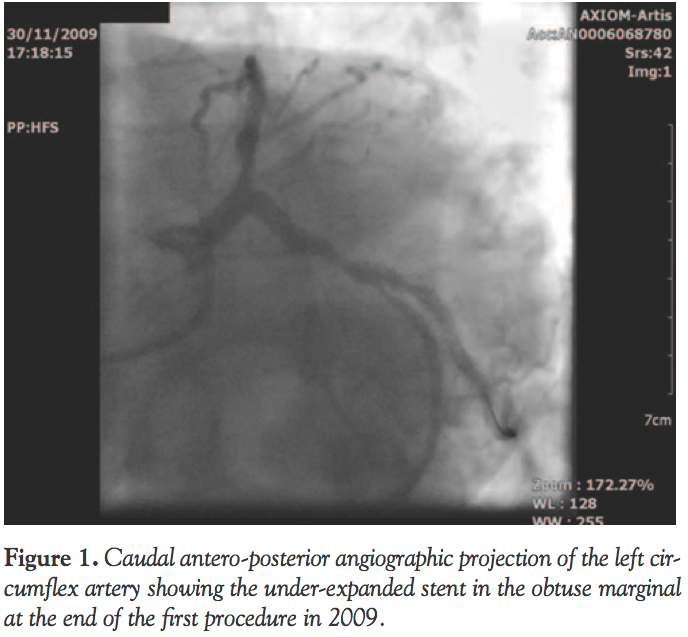

colleague performed PCI to the LAD first with drug-eluting stent (DES) insertion; the OM1 was then wired and predilated with 2.0 balloon and stented with a 2.75 x 28 mm Xience DES (Abbott Vascular), which is a cobalt-chromium stent. It was evident that the stent in the OM1 was under-expanded proximally with a waist. Further postdilatation was performed with 3.0 and 3.5 non-compliant Quantum Maverick balloons (Boston Scientific) to a high pressure of 28 atm, but the stent could not be expanded fully and remained waisted (Figure 1). No further action was taken at the time and the patient was discharged home in a stable condition on dual anti-platelet therapy.